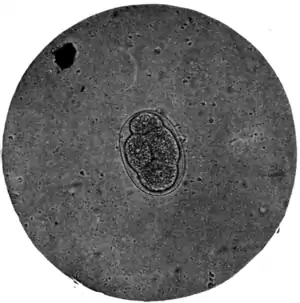

Fig. 173.—Ovum of A. duodenale, x 250. (Photograph by Dr. J. Bell.)

The ova of Ankylostomum duodenale (Fig. 168, b) contrast very markedly with both the foregoing, particularly in the matter of colour. Trichocephalus and ascaris ova are invariably dark and bile-stained; those of the ankylostomum are beautifully clear and transparent; they measure 55 μ to 65 μ by 32 μ to 43 μ; have a regular, somewhat elongated oval form, with a delicate, smooth, transparent shell, through which two, or four, or eight light-grey yolk segments can be distinctly seen. It is well to search for these ova soon after the fæces have been passed; otherwise, owing to the rapidity with which, in favourable circumstances, development proceeds, the embryo may have quitted the shell and the egg be no longer visible.

Diagnosis.— Provided its presence be suspected, ankylostomiasis is easily diagnosed. In tropical countries, in patients coming from tropical countries, and in miners who work in very warm mines in cooler climates, anæmia with concurrent eosinophilia should always suggest a microscopical examination of the fæces. If the ova (Fig. 168, b, e, and Fig. 173) of A. duodenale or of N. americanus are discovered,*[2] and no other reason for the anæmia be made out, the presumption is that one of these parasites is at the root of the mischief; at all events, no harm is likely to result from treatment based on this supposition. On the other hand, if no ova are found it must not be concluded that the case is not one of ankylostomiasis; for it sometimes happens that, in the later stages of the disease, symptoms will persist although the parasites which caused them in the first instance have disappeared spontaneously, or have been got rid of by treatment. Permanent degeneration of the alimentary canal, of the heart, liver, kidneys, and blood-forming organs, may remain, and even prove fatal, although the primary cause is no longer present. The history and the absence of other sources of anæmia are all we may have to go upon for diagnosis in such circumstances.